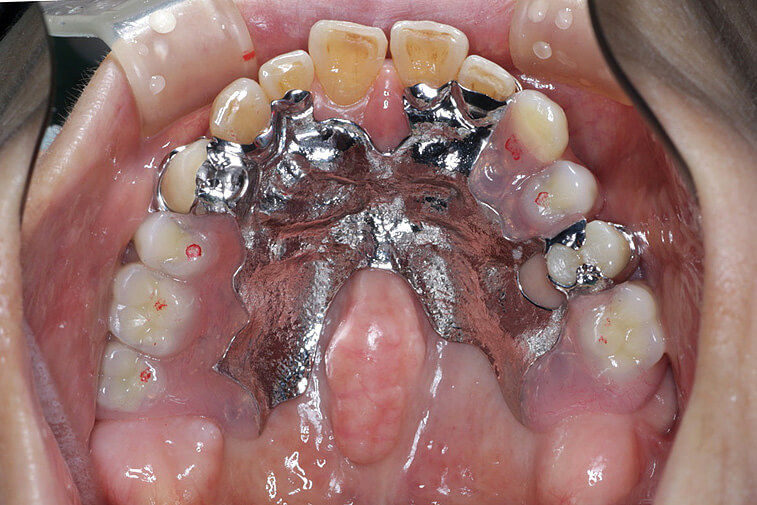

【70歳男性】

入れ歯の不具合と虫歯のお悩みで来院された患者さまに、上顎にコーヌス義歯、下顎にはセラミッククラウンを用いた治療を行いました。

上顎には、見た目が自然で長く使える入れ歯を採用しました。前歯にも違和感なくなじみ、審美性の高さにご満足いただいています。下顎は歯周病や根の治療を丁寧に行ったうえで、セラミックによる修復を実施し、自然な仕上がりを実現しました。

| 主訴 | 入れ歯の不具合と虫歯を治したい。 |

| 治療内容 | 上顎:コーヌス義歯(着脱式) 下顎:セラミッククラウン |

| 治療期間 | 2年間 |

| 治療費 | 約4,000,000円(上下合計) |

| リスク・副作用 | ※予後を完全に保証する治療ではありません。 ※自由診療での治療です。 ※色調を合わせることが難しく、一度で色調が再現できないことがあります。 ※再度色合わせが必要になるケースがあります。 ※精密な装置であるため装置が落としたときに破損するときがあります。 |